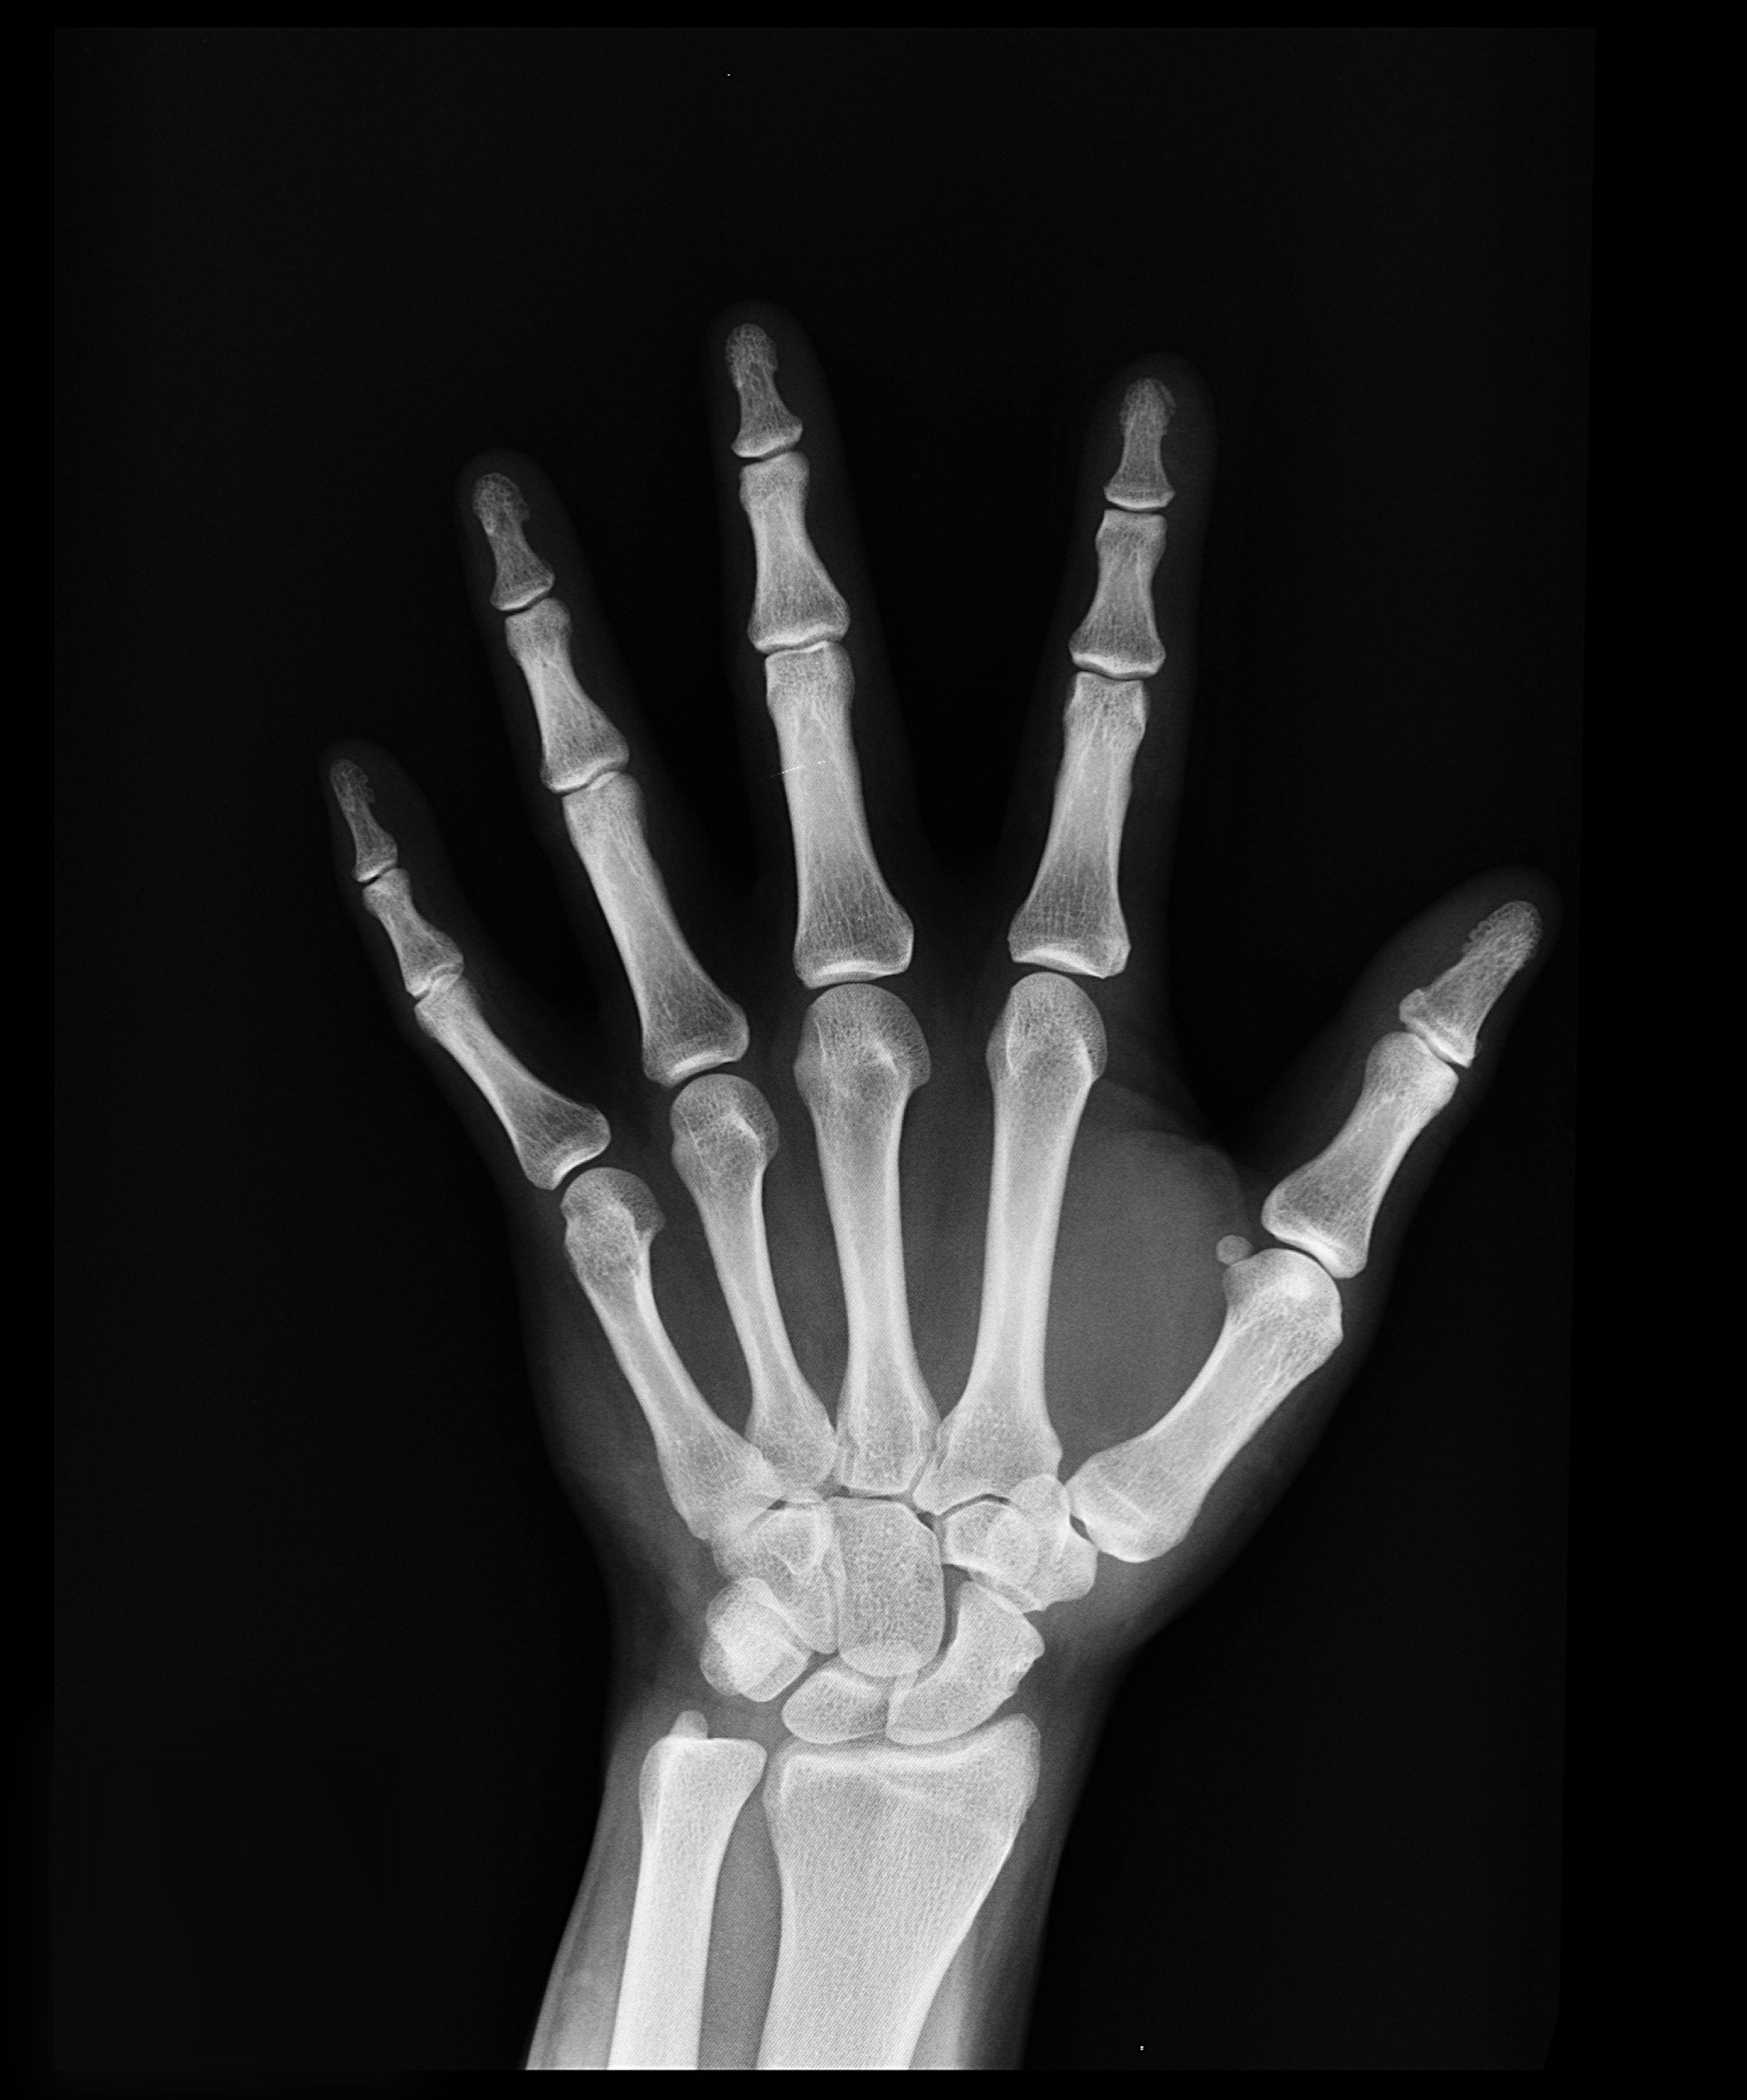

Jameela Jamil, a talented actress, recently came out and shared her diagnosis of having bone density issues after looking into her chronic pain.

“20 years of dieting have damaged my bone density,” she pleaded, “do not let diet culture drag you to where I am.”

Frailty is dangerous. It’s scary. It hurts… It happens sooner than we realize.

No one is more at risk for frailty than a woman going through traumatic, stressful, and confusing health issues, often during the menopausal transition.

Surgery can speed up things like bone and muscle loss, especially if it doesn’t go well.